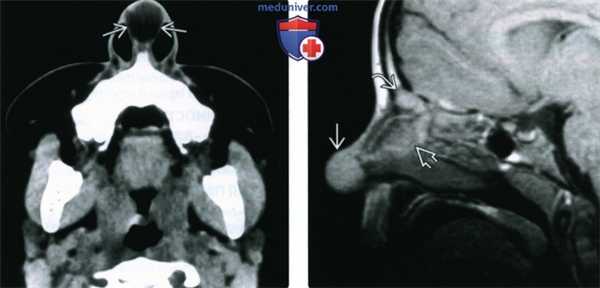

(Слева) При аксиальной КТ без КУ в кончике носа визуализируется хорошо отграниченное объемное образование, сопоставимое с дермоидной кистой, имеющее слегка более высокую плотность, чем окружающий жир. Дермоидные кисты у этого пациента также были обнаружены в носовой перегородке и в слепом отверстии.

(Справа) При сагиттальной МРТ Т1ВИ у этого же пациента визуализируется дермоидная киста в кончике носа; видны другие дермоидные кисты в носовой перегородке и в основании черепа.